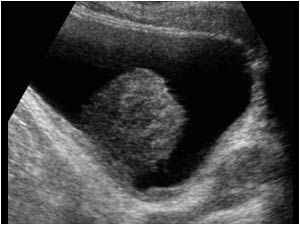

Mesanede kitle ne demek? Mesanede kitle her zaman kanser midir? Mesanede kitle, daha çok ultrasonografi yada tomografi gibi görüntüleme tetkikleri sırasına ait raporlarda yer alan bir ifadedir. Bu ifade ile kastedilen, idrar torbasında anormal bir oluşumdur. Bu oluşum tümör, polip ya da taş gibi farklı sebeplerle meydana gelir. Bu kitlenin kanser olup olmadığı, ancak yapılan testlerle belirlenir. İyi huylu kitleler, genellikle belirti vermez. Kanserli kitleler ise idrar yaparken kanama, ağrı, sık idrara çıkma gibi belirtilerle kendini gösterebilir. Mesanede kitle tespit edilirse, tanı ve tedavi için ileri görüntüleme testleri ve biyopsi işlemleri gerekir.

Mesanede kitle her zaman kanser midir? Bunu anlamak için sistoskopi yapılması gerekir. TUR M işlemi de yapılabilir. Sistoskopi, mesanenin incelenmesi için yapılan bir tıbbi işlemdir. Bu işlemde, ucunda bir kamera bulunan ince, esnek bir tüp (sistoskop) üretradan (idrar yolu) mesaneye yerleştirilir. Sistoskopi, mesane kanseri, enfeksiyon, taş veya polip gibi anormal durumları teşhis etmek amacıyla kullanılır. Ayrıca, bu işlem sırasında biyopsi alınabilir veya küçük cerrahi müdahaleler yapılabilir. Sistoskopi genel veya lokal anestezi altında yapılır ve hastalar çoğu zaman işlem sonrası kısa bir süre içinde normal yaşantılarına dönebilir.